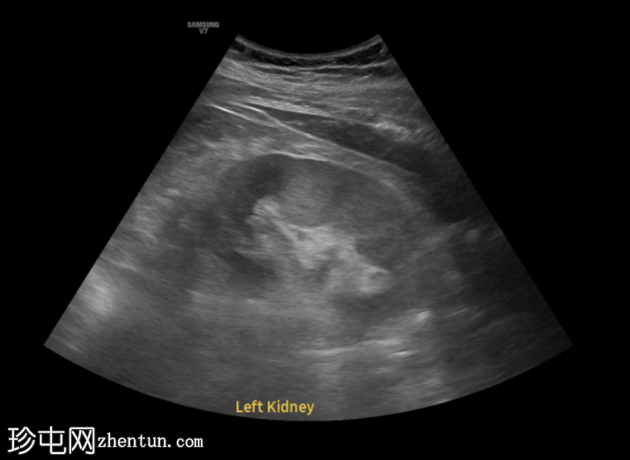

超声显示左侧轻度肾积水,由膀胱输尿管连接处一枚7毫米的远端输尿管结石阻塞所致,输尿管射流正常。

肾积水并非总是由输尿管结石引起。肾盂和肾盏扩张的程度与结石大小并不一定相关。

较小的结石有时可导致中度上游扩张,而较大的结石可能仅引起轻微的充盈感,这取决于患者的引流和水合状态。